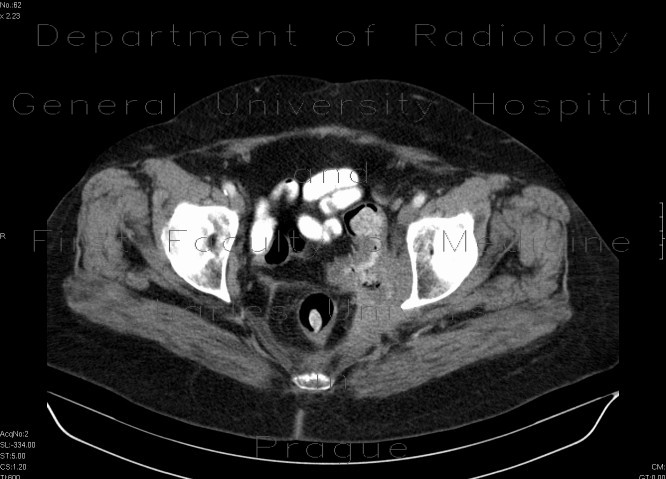

Descending colon stenosis As A Complication Of ... - Termedia

Przegląd Gastroenterologiczny 2009; 4 (1) Descending colon stenosis as a complication of acute pancreatitis Zwê¿enie zstêpnicy jako powik³anie ostrego zapalenia trzustki ... Retrieve Here